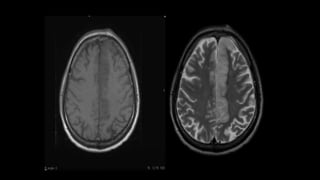

• #46 Here is the example of the same patient shown before. DWI shows hyperintensity in the right frontoparietal region with hypointensity on corresponding ADC map s/o diffusion restriction

• #47 MR 2D ANGIO and 3D TOF MIP images show loss of flow related signals in right MCA. RIGHT ICA appear decreased in calibre as compared to left ICA